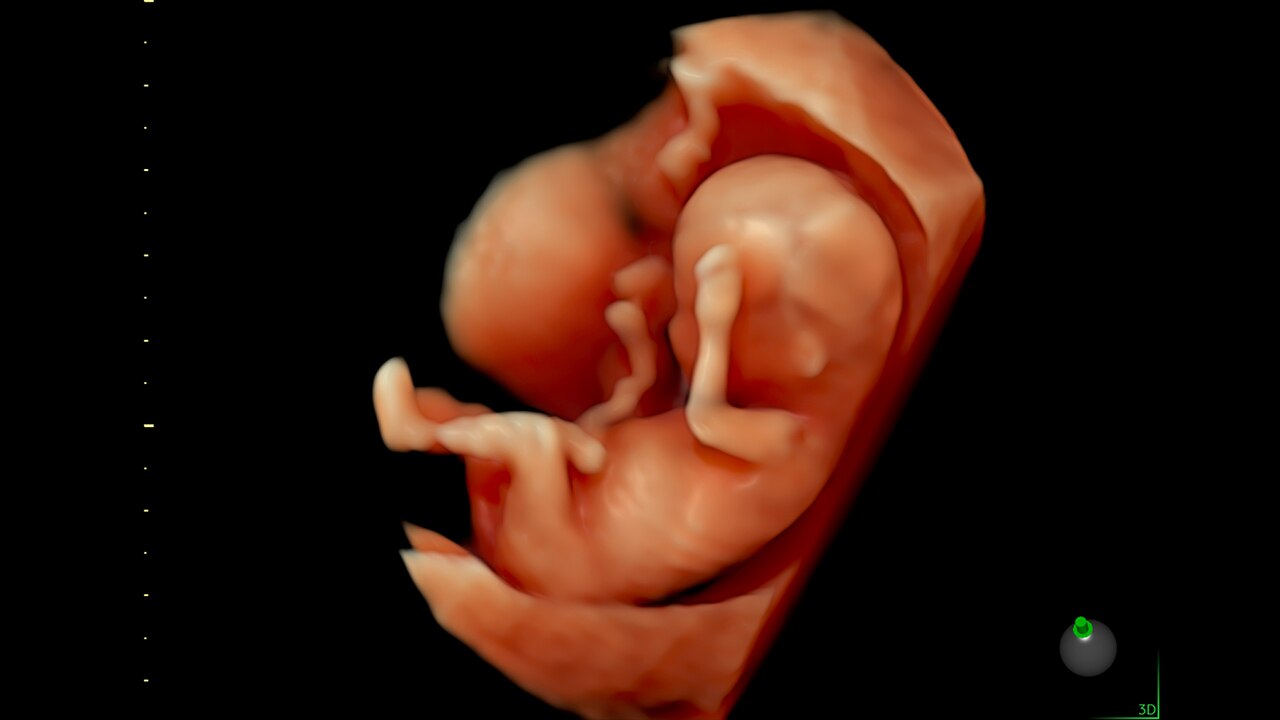

Next level color Doppler that delivers exceptional sensitivity for easy, fast visualization of blood flow, displaying a 3D like appearance as seen in this 27-week fetal heart.